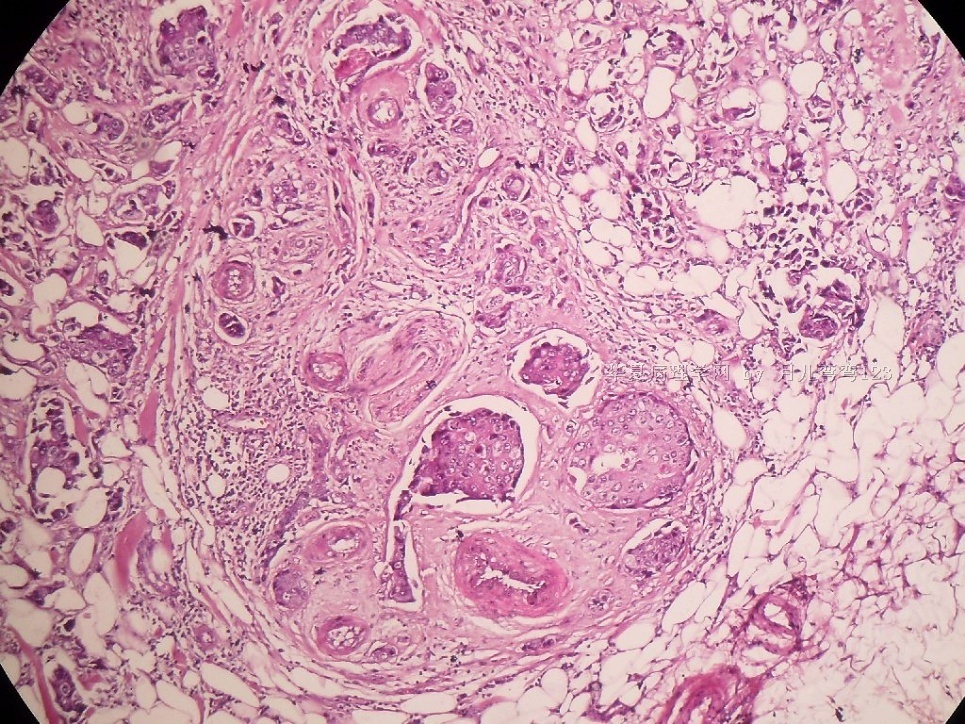

B2778浸润性导管癌?

姓    名: ××× 性别:  女 年龄:  45

标本名称:  左侧近乳晕处肿物

简要病史:  患者描述有疼痛

肉眼检查:  肿物一个2.5*2*1厘米,切面灰白质地硬。

• 浸润性导管癌?图1

• 浸润性导管癌?图2

图2

上皮样细胞,大部分粘附成团成巢,明显浸润。大部分细胞大,核级别高,少数图中见松散的小细胞。未见原位癌。

大细胞考虑浸润性导管癌(3级),小细胞要排除小叶癌。如果有条件请做免疫组化。

应该是浸润性导管癌,标本可能有部分自溶现象。